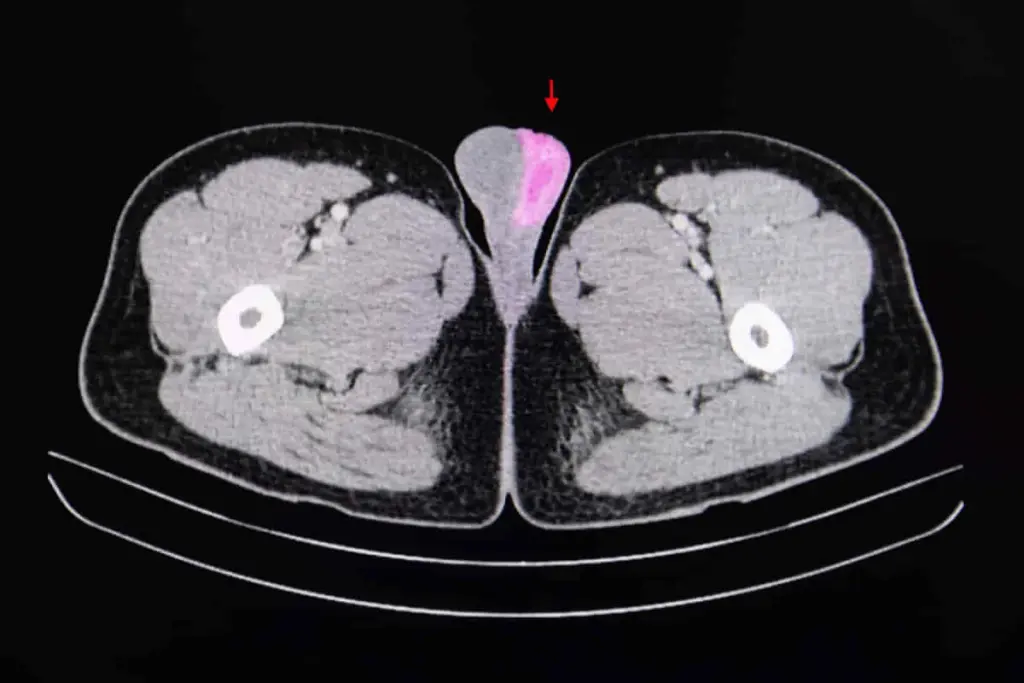

Imaging Tests Used in Diagnosis

If a physical exam finds something unusual, imaging tests are used to look closer. Ultrasound is a common test to check the testicles and nearby areas. It can spot tumors, cysts, or other issues that a physical exam might miss.

Ultrasound is a safe way to get important information for diagnosis. It helps doctors understand what they found during the physical exam.